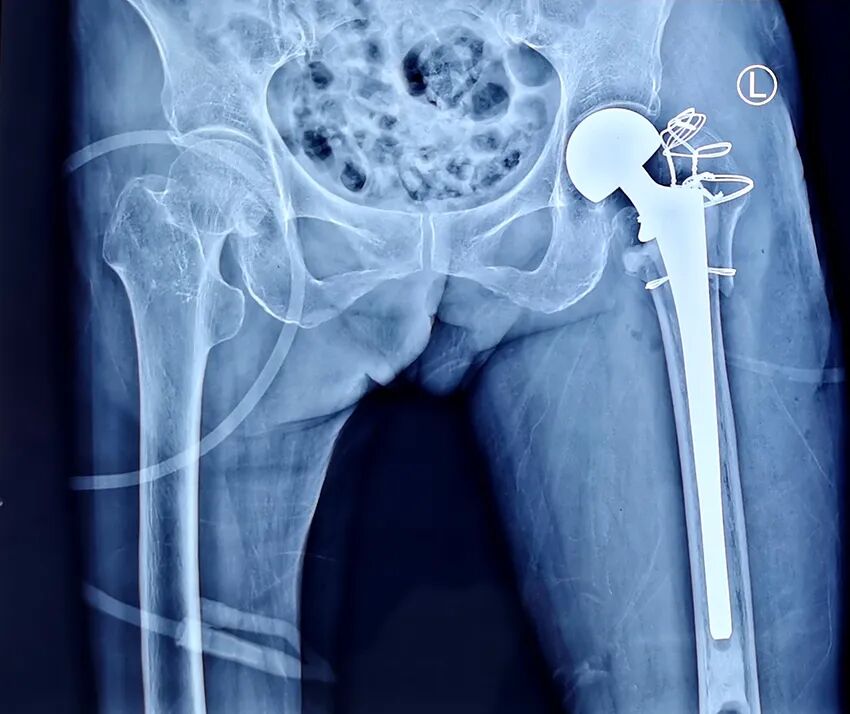

患者余某,男性,今年92岁,家住雷州纪家镇某村。

入院:2022年10月2日;出院:2022年10月19日。

术前图像

术后图像